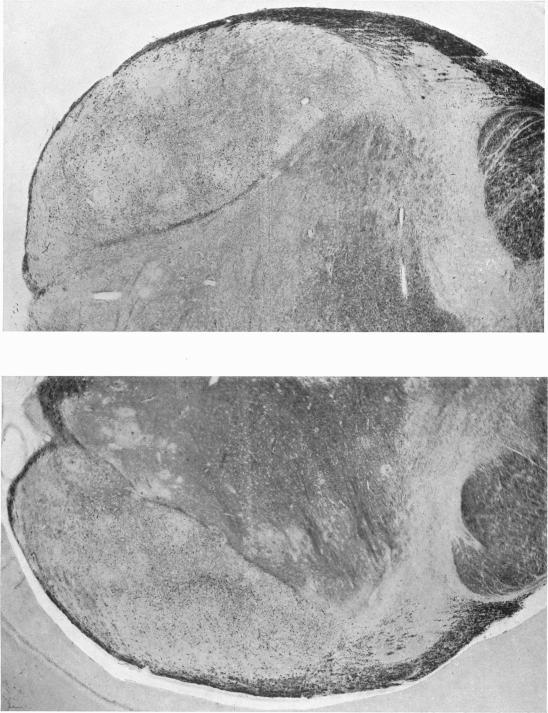

A study of the subcortical connexions of the optic tract system of the ferret, with special reference to gonadal activation by retinal stimulation.

J Anat. 1940 Oct;75(Pt 1):106-134.3.